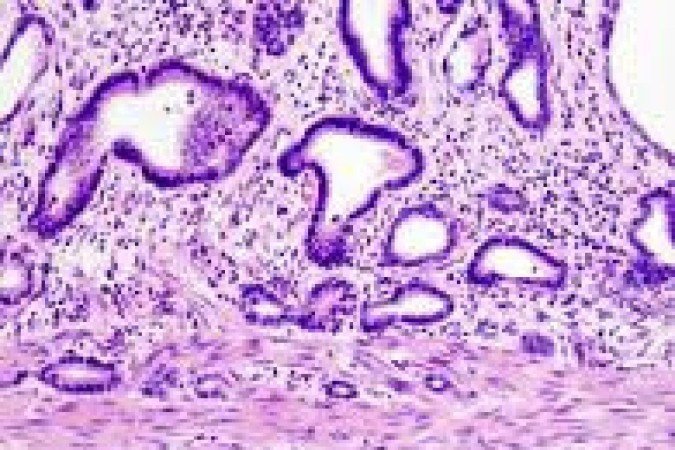

As células T CD8+ são conhecidas como os "soldados" do sistema imunológico. Elas reconhecem e atacam células tumorais. O problema é que, quando ficam expostas por muito tempo ao câncer, entram em um estado chamado exaustão, em que perdem força, energia e capacidade de combater o tumor. O estudo mostra que esse processo acontece por causa de um "efeito dominó" dentro da própria célula.

A exaustão das células T é um dos principais desafios da imunoterapia, tratamento que estimula o próprio sistema imunológico do paciente a atacar o câncer. Hoje, parte das terapias funciona bem no início, mas pode perder efeito quando as células entram nesse estado de “cansaço terminal”. Entender o que causa esse bloqueio ajuda a pensar em novas soluções.